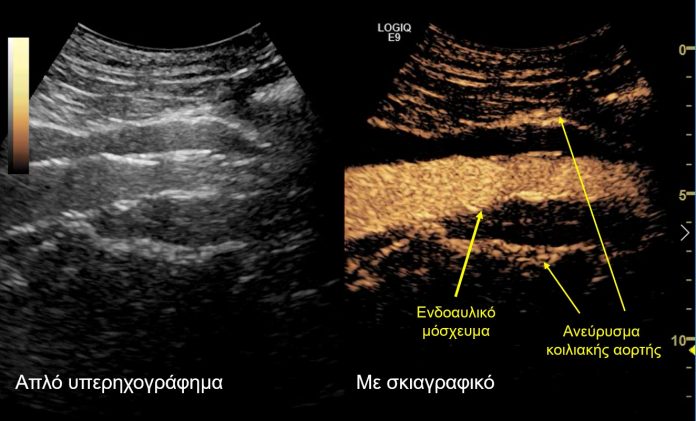

Σε αυτό το πλαίσιο εντάσσεται και ο μετεγχειρητικός υπερηχογραφικός έλεγχος που διεξήχθη στο Τμήμα Υπερήχων από τη Δρ. Κωνσταντίνα Κυριακοπούλου, MD, PhD,  Διευθύντρια Τμήματος Υπερήχων, Ιατρικό Κέντρο Αθηνών και τον Ταξιάρχη Καράμπελα, MD, Ακτινολόγο, Αναπληρωτή Διευθυντή Τμήματος Υπερήχων, Ιατρικό Κέντρο Αθηνών. Το κέντρο αυτό ανήκει στα ελάχιστα ευρωπαϊκά κέντρα, τα οποία ελέγχουν τη βατότητα των σπλαγχνικών αγγείων και την επιτυχή ενδοαγγειακή αποκατάσταση των ανευρύσματων υπερηχογραφικά, με τη χρήση ειδικού σκιαγραφικού (SonoVue) που μεταβολίζεται αποκλειστικά στο ήπαρ. Αυτό αποτελεί ιδιαίτερο πλεονέκτημα σε ασθενείς με επηρεασμένη νεφρική λειτουργία.